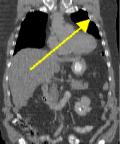

Patient below has a history of prostate cancer and melanoma with known metastasis to T7.   PET scan was performed to rule out radiation changes versus recurrence at T7.   The PET scan was negative in T7 (thus compatible with radiation changes) but serendipitously revealed marked uptake in the left upper hemithorax (Fig. 1-2 coronal and axial PET tomograms).   A subsequent CT with coronal reformation demonstrated a destructive rib lesion consistent with metastasis (Fig. 3-4).   This changed patient management who subsequently underwent chemotherapy.

Figure 1Figure 2Figure 3Figure 4